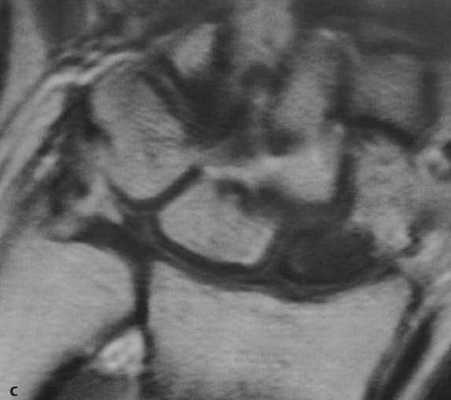

а-d Перелом ладьевидной кости. МРТ. (а) Неконтрастное Т1-взвешенное изображение демонстрирует распространенные участки снижения интенсивности сигнала.

(b) Последовательность SТ1R демонстрирует гиперинтенсивный сигнал с гипоинтенсивной линией перелома.

(с) Т1 -взвешенное изображение после введения контрастного вещества. Проксимальная часть ладьевидной кости не накапливает контрастное вещество, что означает нарушение кровоснабжения и лишение жизнеспособности.

(d) Длительно существующий некроз ладьевидной кости с резорбцией проксимального фрагмента, дегенеративными изменениями, поражающими лучезапястный сустав с нестабильностью запястья и уменьшением высоты запястья.